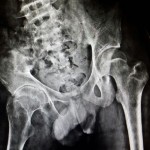

Image Challenge 13, Paediatric #Hip

Popular Answer may not imply right answer, Follow our twitter handle for the right answer, Click for Answer